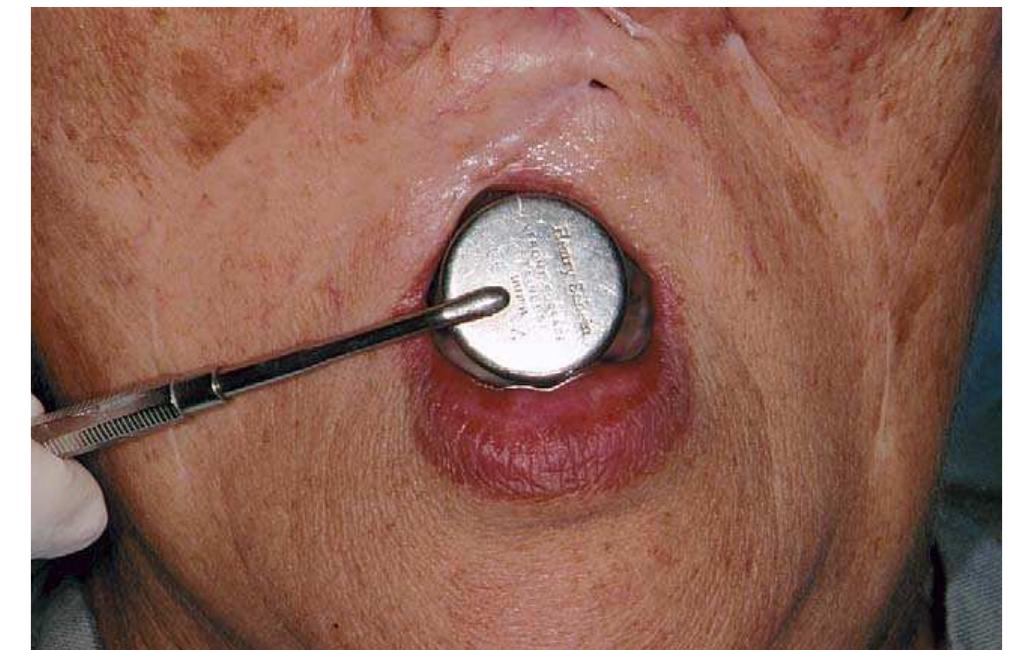

Limited oral access presents a unique challenge to prosthodontic treatment. An edentulous patient who developed microstomia after a maxillary lip resection is presented. The clinical procedure and the rationale for the treatment approach... more